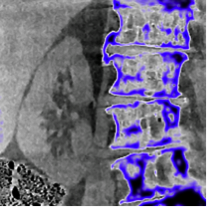

Advances in CT Imaging, Dose Reduction, and Image Quality

This year marks the 25th anniversary of spiral CT, and ongoing advances in scanner technology, mathematical algorithms, and high-speed computing are converging in a way to advance CT performance while minimizing radiation dose. Advances include: the use of previous CT scans of the same patient to improve quality and reduce subsequent scans; the use of mathematical algorithms to decrease image noise; the use of image-guided surgery to improve surgical guidance and reduce dose; and measuring and modeling image quality to identify dose limits in a manner consistent with the imaging task. In an invited symposium on Monday, July 21, experts from the University of Wisconsin, University of Chicago, Johns Hopkins University, and Duke University present the latest research in these rapidly advancing areas of CT image quality.

This year marks the 25th anniversary of spiral CT, and ongoing advances in scanner technology, mathematical algorithms, and high-speed computing are converging in a way to advance CT performance while minimizing radiation dose. Advances include: the use of previous CT scans of the same patient to improve quality and reduce subsequent scans; the use of mathematical algorithms to decrease image noise; the use of image-guided surgery to improve surgical guidance and reduce dose; and measuring and modeling image quality to identify dose limits in a manner consistent with the imaging task. In an invited symposium on Monday, July 21, experts from the University of Wisconsin, University of Chicago, Johns Hopkins University, and Duke University present the latest research in these rapidly advancing areas of CT image quality.